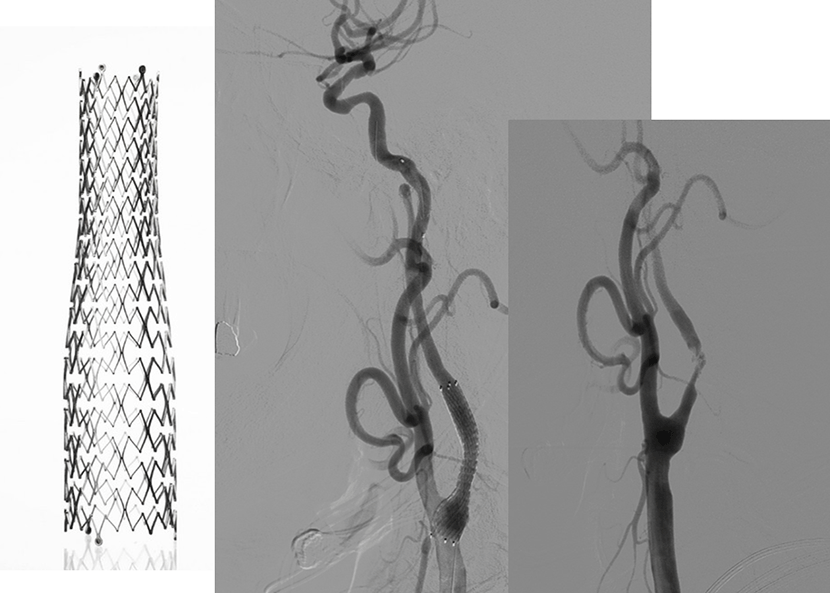

뇌동맥류에 대한 혈관내수술과 개두술후 결찰술, 내경동맥 협착증의 풍선성형술 및 스텐트삽입술, 동정맥기형에 대해 오닉스 색전술, 급선뇌경색에서 약물을 이용한 혈전용해술과 기계적 혈전제거술, 두개내압항진시 감압개두술 등 다양한 치료를 시행하고 있습니다.

뇌MRA 와 뇌혈관조영술에서 좌측내경동맥의 심한 협착이 보임

성형술과 스텐트 삽입술을 시행하여, 우측의 수술전 사진과 비교시, 혈관을 넓혀주어 추가적인 뇌경색을 예방